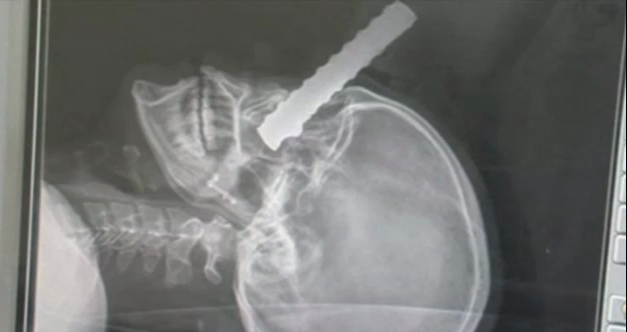

Es ist ein Wunder: Eine zwei Meter lange Eisenstange durchbohrte den Kopf von Eduardo Leite (24) aus Brasilien – und der Bauarbeiter hat es überlebt!